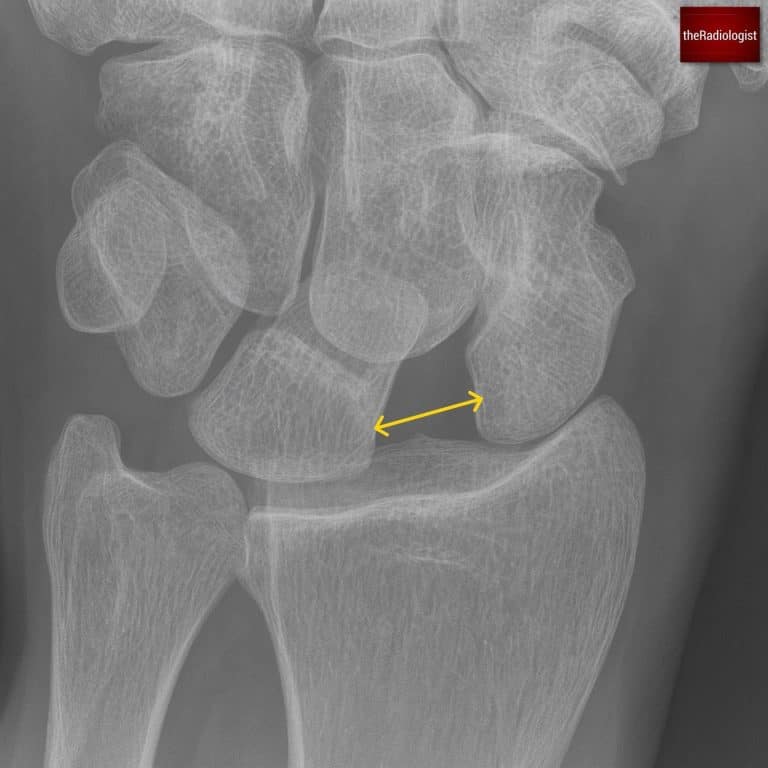

Beyond the scaphoid, check that the spaces between all the carpal bones are equal and less than two millimetres. A widened scapholunate gap can indicate scapholunate dissociation, sometimes called the Terry Thomas sign, named after a English actor in the 50s/60s who had a gap between his front teeth. In America this is also known as the David Letterman sign.

Widening of the gap between the scaphoid and lunate bones point towards scapholunate dissociation.

Make sure the lunate has its usual quadrangular shape; a triangular appearance can be a clue to perilunate dislocation. We will go through lunate and perilunate dislocation in a bit more detail below in the lateral X-Ray section.